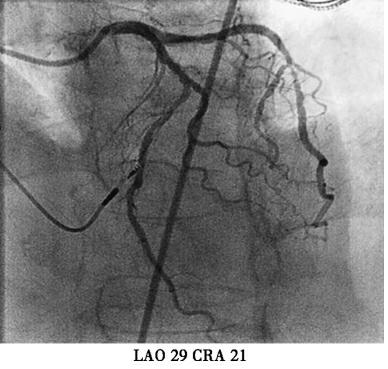

本例患者虽然有高血压、糖尿病等冠心病危险因素。起搏器电极植入后立刻发生的胸痛考虑与心绞痛关系不大,且患者未出现心电导联ST-T变化,胸痛原因主要考虑:起搏电极导致冠脉损伤?起搏电极刺破右室?遂台上决定立即行冠脉造影(图3);多个投照体位均可见起搏电极螺旋尖端触及前降支,因此决定行前降支血管内超声(IVUS)检查,结果于电极接触部位,血管8点钟方向可见强回声,距离血管外膜小于1mm;综合判断起搏电极损伤血管外膜导致胸痛的可能性大;随后进行电极重新植入,并再次造影排除起搏电极穿透冠脉可能,电极具体位置及冠脉造影见图4,心室起搏参数(阈值0.8V,阻抗670Ω,R波10.0mv)。患者症状完全消失,于导管室留观30分钟,复查心脏超声,心包内未见积液,排除起搏电极刺破右室可能,转回病房。

图4重新植入心室电极后冠脉造影